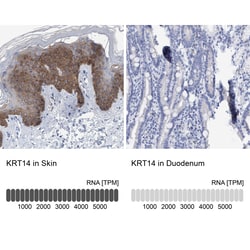

Cytokeratins (CK) are intermediate filaments of epithelial cells, both in keratinizing tissue (ie. skin) and non-keratinizing cells (ie. mesothelial cells). At least 20 different CKs can be identified. Biochemically, most members of the CK family fall into one of two classes, type I (acidic polypeptides) and type II (basic polypeptides). Belonging to the type I subfamily of low molecular weight keratins and existing in combination with keratin 5, keratin 14 distinguishes stratified epithelial cells from simple epithelial cells and is useful in identification of squamous cell carcinomas. It is considered a prognostic marker in breast carcinomas. At least one member of the acidic family and one member of the basic family is expressed in all epithelial cells.

| Applications | Immunohistochemistry (Paraffin), Western Blot |

| Gene | KRT14 |